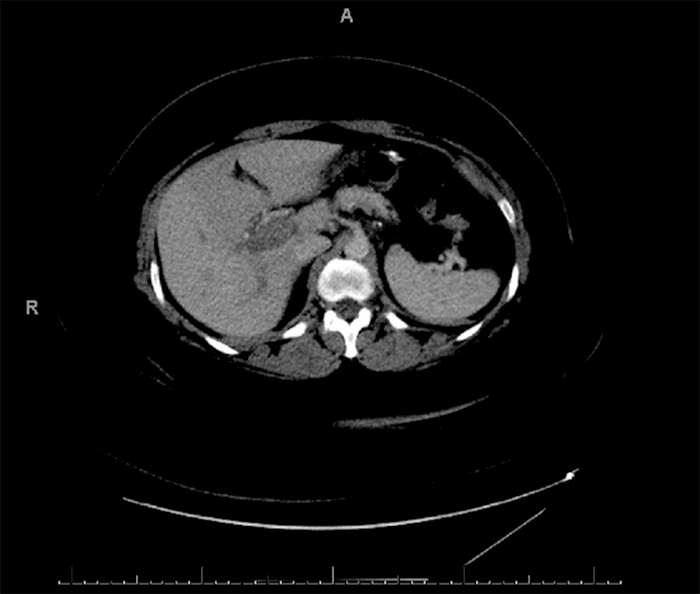

A 46-year-old morbidly obese African American woman presented with abdominal pain 13 days postlaparoscopic sleeve gastrectomy. Her pain was central and sharp in quality. She denied nausea, vomiting, or change in bowel habits. She also denied fever, chills, or dysuria. She was afebrile, hemodynamically stable, and her body mass index was 42.92. She had diffuse tenderness to deep palpation but did not exhibit peritoneal signs on exam. Labs were pertinent for mild leukocytosis, but electrolytes, blood urea nitrogen, and creatinine were within normal limits. Computed tomography (CT) of the abdomen and pelvis (Figure 1 and Figure 2) were suggestive of extensive portal vein thrombosis (PVT) that was confirmed with a follow-up ultrasound doppler study showing no flow in both branches as well as in the main portal vein (Figure 3 and Figure 4).

Twenty days following thrombolysis, the patient underwent magnetic resonance cholangiopancreatography (MRCP) for reasons unrelated to this case, and the results showed persistent thrombus in the main portal vein (Figure 5).

Figure 5. MRCP showing stable thrombus in the main portal vein (arrow).

Figure 6. Repeat CT at six-month follow-up shows serpiginous vessels highly suggestive of portal cavernoma.